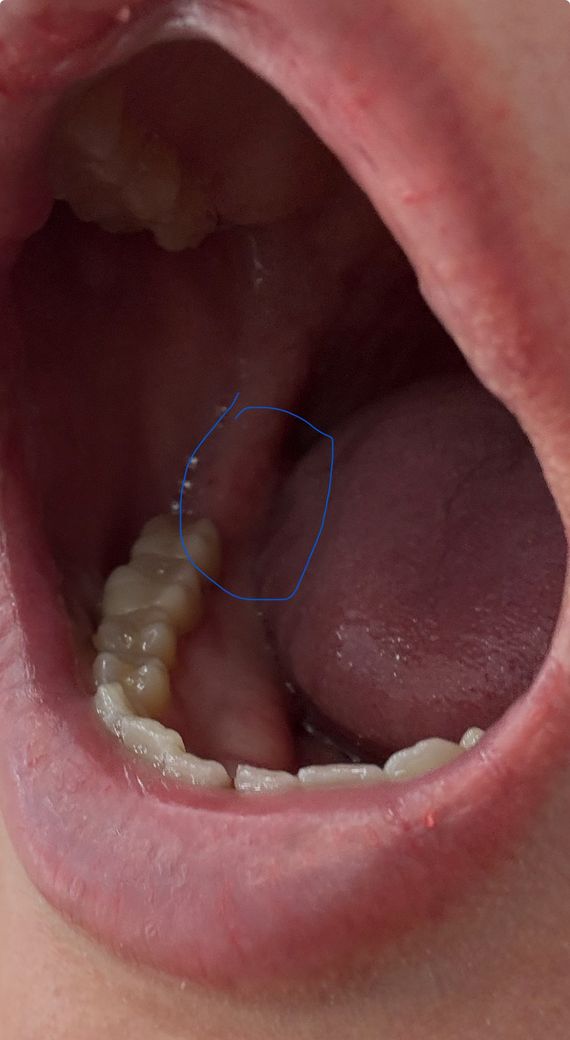

사랑니 뺀자리 구내염 같은게 생겼어요

정확히 언제 부터인지 알 수 없지만 사랑니 뺀 후 사진에서 처럼 저 부위에 구내염처럼 뭐가 생겼어요 ㅜ

• 1번 째 사진